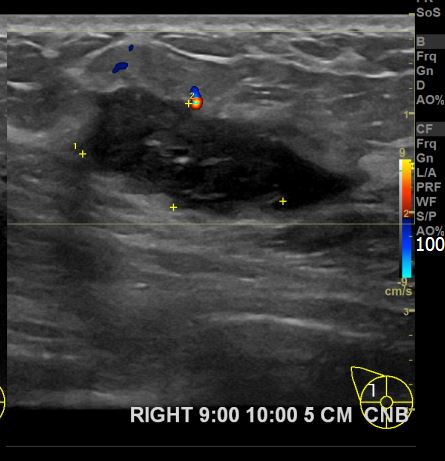

아산유외과 개원후 763번째 유방암진단

상기환자 외부검사상 이상소견으로 내원하신 50대 후반 여성분으로 우측 조직검사 시행해 침윤성 유방암으로 진단되었습니다